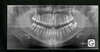

Tout d'abord, le praticien va procéder à un examen du patient (examen clinique). Des examens complémentaires tels que moulage des dents, photographies intra-buccales et faciales seront effectués au cabinet. Des documents radiologiques complémentaires (souvent une radiographie panoramique, une téléradiographie de profil, parfois une radiographie du poignet pour déterminer l'âge osseux, c'est-à-dire situer un patient sur sa courbe de croissance) sont également nécessaires à la planification du traitement. L’état des dents et des gencives sera regardé avec attention.

Tous ces éléments : radiographies, moulages, photographies..., font partie de ce que l'on appelle le dossier orthodontique.